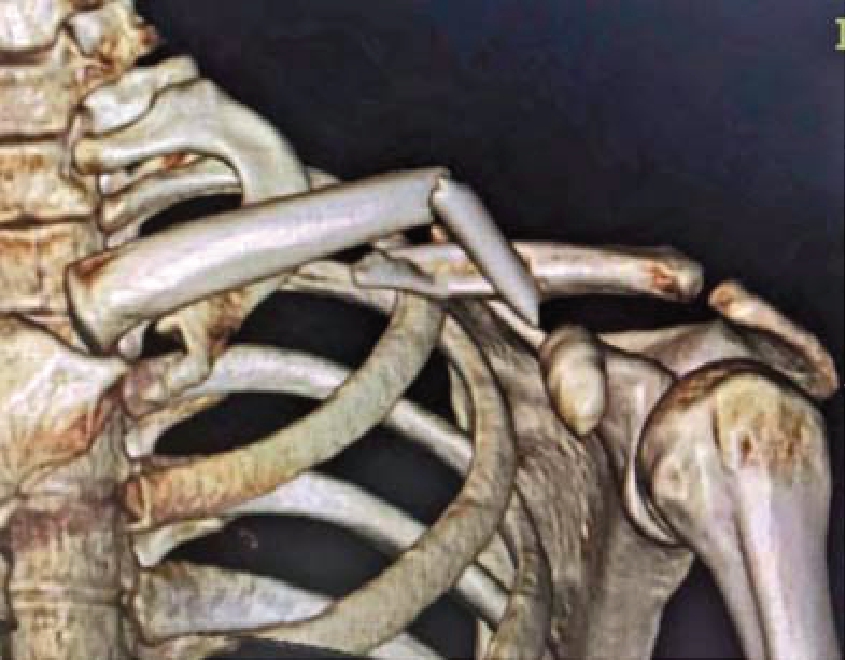

X线检查为锁骨骨折首选的检查方法[10]。最常用的摄影体位为锁骨后前位,拍摄范围应包括锁骨全长、肱骨上1/3、肩胛带及上肺野,必要时需另拍摄胸片。前后位像可显示锁骨骨折的上下移位,45°斜位像可观察骨折的前后移位(图1—2)。CT检查多用于复杂的锁骨骨折,如波及关节面及肩峰的骨折。尤其对于累及关节面的骨折,CT检查优于X线检查。三维重建CT图像可清楚地显示锁骨骨折块的移位情况(图1—3)。

图1—3 锁骨中段骨折CT三维重建